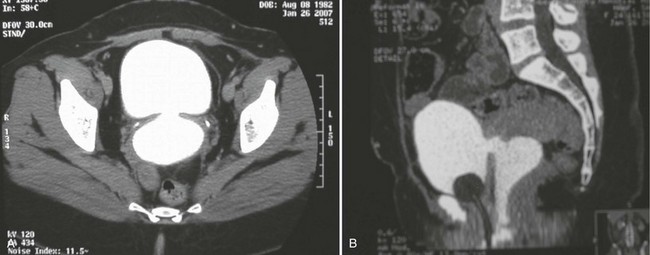

In addition to contrast cystography and VCUG, CT, ultrasonography, and magnetic resonance imaging (MRI) have been used in the evaluation of VVF (Kuhlman and Fishman, 1990; Outwater and Schiebler, 1993; Yang et al, 1994). Delayed CT visualization of contrast within the vagina is considered highly suspicious for VVF in the majority of cases (Kuhlman and Fishman, 1990) (Fig. 77–10). In cases of suspected VVF, CT should be performed with only intravenous contrast, or, alternatively, a CT cystogram can be performed to isolate the bladder. A vaginal tampon placed per vagina during IVU or CT scan may improve the sensitivity for finding small or occult VVF in patients with an otherwise negative evaluation (Wesolowski and Meaney, 1977). Cross-sectional imaging may also be helpful in assessing for recurrent malignant disease in those with such a history.

Figure 77–10 CT scan of vesicovaginal fistula (VVF). A, After intravenous administration of the contrast agent, there is high-density material in both the bladder and vagina consistent with a VVF. The fistulous connection between the bladder anteriorly and the vagina posteriorly. B, Sagittal CT reconstruction demonstrating VVF.